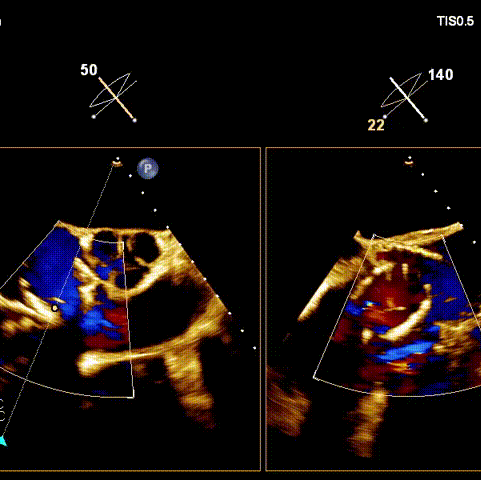

術后超聲

術前經(jīng)過全面系統(tǒng)的評估后,考慮患者存在高齡、心功能減低、三尖瓣瓣環(huán)重度擴張(三尖瓣極重度反流)等高危因素,因此廈心結構心團隊聯(lián)合超聲心動、麻醉及護理團隊,制定了詳盡的圍術期治療方案及術中治療難點預案。術中,由王焱院長主刀,在蘇茂龍主任超聲心動團隊的輔助,上海市第一人民醫(yī)院陸方林主任的協(xié)助下,僅用時30分鐘,即順利完成了三尖瓣原位置換的手術。術中患者血流動力學穩(wěn)定,術后即刻顯示LuX-Valve Plus瓣膜位置良好,固定穩(wěn)定,瓣膜功能正常,無瓣周漏。

觀摩手術的臺灣專家對此次手術過程及LuX-Valve Plus器械展示出的優(yōu)異性能表示贊譽,表示與傳統(tǒng)外科三尖瓣治療方式相比,LuX-Valve Plus介入三尖瓣治療創(chuàng)傷小,安全性高,手術時間短,術中術后患者血流動力學可平穩(wěn)過渡;且與現(xiàn)有的三尖瓣緣對緣修復手術相比,LuX-Valve Plus原位三尖瓣置換對術中影像依賴度相對更低,操作更加便捷,并且憑借獨特的錨定及瓣葉固定方式可以最大程度的避免高度房室傳導阻滯的發(fā)生,同時也擁有較為豐富的產(chǎn)品規(guī)格,可以適應不同三尖瓣瓣環(huán)擴張程度的患者,自適應防漏環(huán)還可以有效預防瓣周漏的發(fā)生,產(chǎn)品的諸多特點讓與會專家再次對國產(chǎn)原創(chuàng)醫(yī)療器械刮目相看,并期望可以早日引入海峽對岸,讓臺灣地區(qū)的患者也可以使用到祖國的原創(chuàng)器械,救治更多的患者。